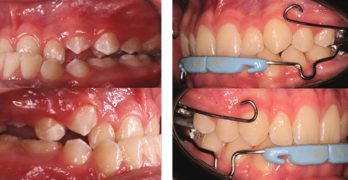

Transformación Estética y Funcional en Maloclusiones Clase II División 2 con el Carriere Motion

El artículo que compartimos el día de hoy se llama Management of Class II division 2 patient treated with Carriere … [Leer más...] acerca de Transformación Estética y Funcional en Maloclusiones Clase II División 2 con el Carriere Motion